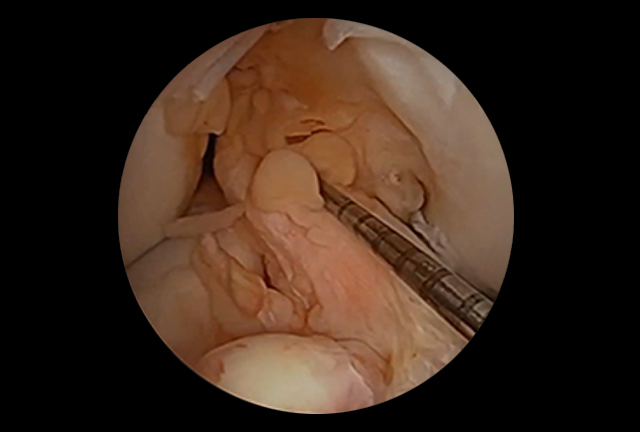

. Arthroscopic Anterior Cruciate Ligament (ACL) Reconstruction

. Meniscal Repair and Cartilage Resurfacing Techniques

There are many controversial choices when it comes to selecting a graft for ACL reconstructive surgery. Though there are other graft options including Hamstring tendons, Quadriceps tendon or Cadaveric tissue, "Autologous" Bone-Patella tendon-Bone is considered the gold standard for high level athletes that participate in twisting, pivoting and deceleration type sports.

In most instances, surgeons will choose a graft type irrespective of a patient’s level of activity. This is usually consistent with a technique learned during their fellowship training, ease of graft harvest (hamstrings) or their desire to use pre-formed cadaveric tissue graft . Having trained in all harvest techniques, I truly believe that autologous Bone-Patella tendon-Bone graft is the graft of choice.

Several studies by the American Journal of Sports Medicine, have confirmed that Hamstring tendon use in ACL reconstructive surgery has a higher incidence of failure, knee joint laxity, infection, arthritis, delayed healing time, graft slippage and hamstring weakness (most noted in deceleration type activities). Although hamstring graft may be considered on occasion in the skeletally immature athlete, it is often considered as a graft option for the low demand, non-contact athlete. The literature also supports that the use of cadaveric tissue in the young high demand athlete has an extremely high failure rate.

Upon review of surgeon's graft choices throughout the nation, more than 75% of surgeons utilize autologous Bone-Patella tendon-Bone grafts during ACL reconstructive procedures in professional and/or collegiate athletes. This graft has been described as having a lower incidence of failure, better fixation, quicker incorporation into bone and the highest rate of return to full pre-injury activities, including sports.

Over the last 20 years, I have used Bone-Patella tendon-Bone in the majority of my high level athletes. There has been no reported weakness subsequent to harvesting this graft type. Although prior literature describes that this technique may predispose a patient to occasional anterior knee pain and/or tendinitis, with careful graft harvest, bone grafting to the patella defect and repair of the patella tendon site, these postoperative symptoms have become negligible.

It is true that surgeon experience, state-of-the-art anatomic technique and proper fixation/ tensioning methods have a significant bearing on the results of this procedure; but there is also enough evidence supporting that proper graft choice significantly contributes to the athletes’ ability to return to sports at a competitive level with excellent long-term results.